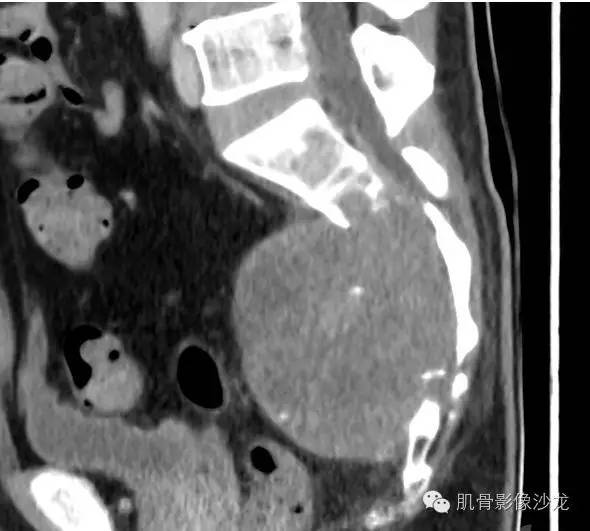

影像表现:骶骨中下部见溶骨性骨质破坏,破坏区见软组织肿块影,边缘无硬化,其内密度不均,可见散在钙化灶,未见骶管、骶孔扩大;强化轻,未见明显坏死。

1、发病部位,有利于脊索瘤的诊断,不利于骨巨的诊断。

2、内可见钙化,有利于脊索瘤的诊断,不利于骨巨的诊断。

夏威夷的风 21:40

最后病理:脊索瘤。